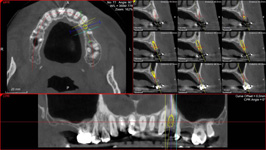

• Navigovaná implantace - navigated surgery - dynamická navigace

- operace je "z volné ruky" a postup se vizuálně kontroluje na monitorech.

• Řízená implantace - guided surgery – statická navigace

- operace pomocí OP šablon. Ve speciálním programu coDiagnostiX se využívají data z CB CT scanu - tedy údaje o množství a kvalitě kosti, dále data získaná ze scanu modelu čelistí s modelem plánované protetické náhrady (korunky, můstku…)

- tedy údaje tloušťce sliznice, pozice a tvaru náhrady.

Tím máme všechny potřebné údaje pro plánování pozic implantátů, jejich potřebné délce a průměru. Abychom mohli implantáty zavést do naplánovaných pozic v ústech pacienta, umožňuje tento program vymodelovat speciální operační šablonu, která je zhotovena 3D tiskárnou. Pomocí této šablony, která se umístí do úst pacienta, pak probíhá vlastní operace

- zavádění implantátů.